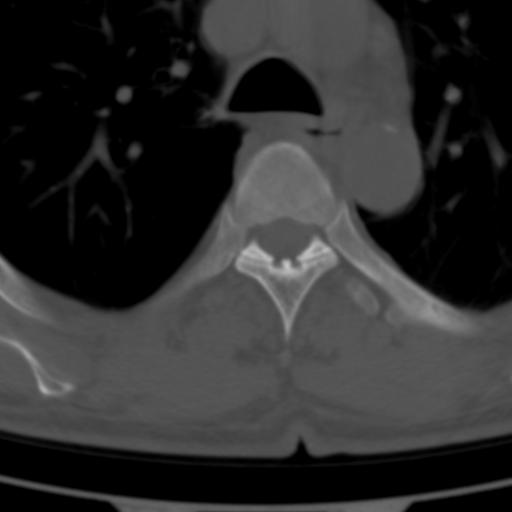

标题: CT25189:胸椎ct,请会诊!

既往食管癌,现行ct检查!

仅见椎体退行性改变

中上段食道癌,椎体轻度退变。

椎体退行性改变,食管癌。